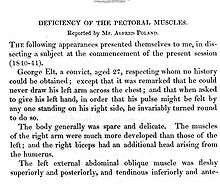

It was first named in 1962 by Patrick Clarkson, a New Zealand-born British plastic surgeon working at Guy's Hospital and Queen Mary's Hospital, London. He noticed that three of his patients had both a hand deformity and an underdeveloped breast on the same side. He discussed this with his colleague at Guy's Hospital, Dr Philip Evans, who agreed that the syndrome was "not widely appreciated". Clarkson found a reference to a similar deformity published by Alfred Poland, over a hundred years earlier in Guy's Hospital reports, in 1841.[13] Clarkson was able to find the hand specimen dissected by Poland, which was still held in the hospital pathology museum.

Poland had dissected a convict known as George Elt, who was said to be unable to draw his hand across his chest. Poland noted the chest wall deformity, and this was illustrated in his article; the hand was also dissected and preserved for posterity in Guy's Hospital museum where it remains today. It cannot be truly said that Poland described this syndrome because he only described one isolated case. Clarkson published his series of three cases and named the syndrome after Poland in his article.[14]

- ↑ Poland A (1841). "Deficiency of the pectoral muscles". Guy's Hospital Reports. VI: 191–193.